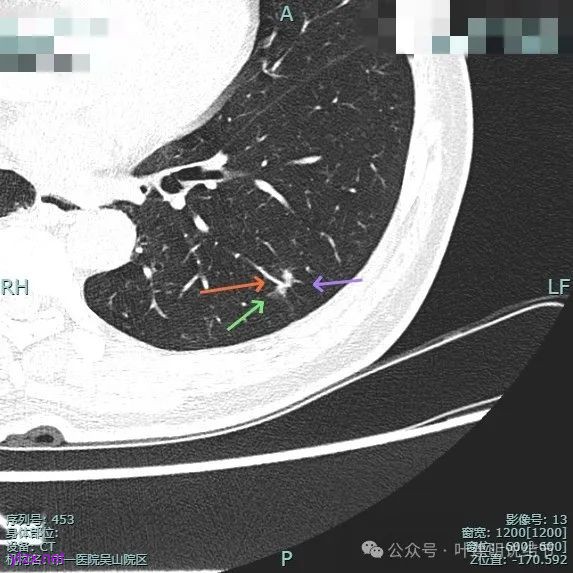

实性成分密度较高,边上有淡磨玻璃成分,毛刺明显。

密度高,边上磨玻璃成分淡,表面不平,毛刺不太锐利,整体感觉缺乏收缩力。

进入的血管没有异常增粗,棘突不太锐利,磨玻璃成分偏糊。

上图倒是血管显得有点异常增粗的,总体膨胀性不强,收缩力不够。